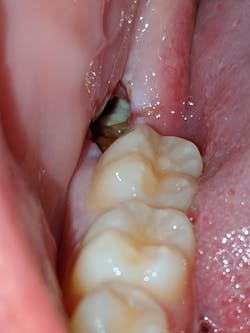

Alveolar osteitis or “dry socket” is one of the most common complications associated with extraction of teeth, especially mandibular third molars. The pathophysiology, causes, and treatment are often debated even to this day due to a complex and multifactorial etiology which is why I have cited a single comprehensive review. Birn, in a series of articles from 1963–1977, noted the pathophysiology of alveolar osteitis to be a fibrinolysis of the postextraction blood clot within the extraction socket. Dissolution and/or exfoliation of the blood clot, before the formation of sufficient granulation tissues, then exposes the remaining alveolar bone and associated nerves within the extraction site to air, debris, bacteria, and saliva which may irritate the area, producing symptoms for the patient. The result is pain, which may be localized or radiate to the ear, possible swelling of the area, and occasionally a bad odor in the mouth.

Treatment of alveolar osteitis, in my experience, consists of debriding the area with irrigation of the site and, if necessary, instrumentation of the socket to remove debris from the site. An obtundent dressing is then placed into the extraction site using Iodoform gauze or Gelfoam as a carrier. The medicament compound placed onto the carrier/dressing varies by personal preference. These compounds usually consist of an analgesic (eugenol), topical anesthetic (benzocaine), and antimicrobial (Iodoform). This dressing covers and quiets exposed nerves and physically prevents debris from entering the extraction site.